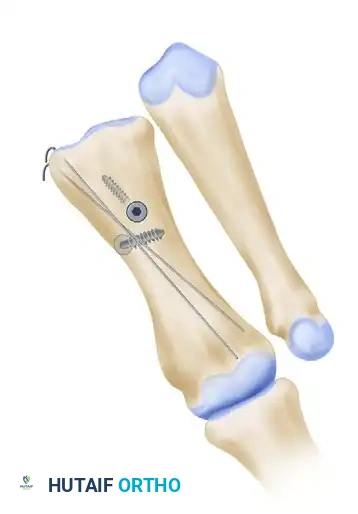

تنفيذ القطع العظمي على شكل حرف زي

الخطوة الجوهرية في العملية هي القطع العظمي الثلاثي على شكل حرف Z. يقوم الجراح بعمل قطع طولي في منتصف العظمة، يليه قطعان عرضيان متوازيان عند طرفي القطع الطولي. دقة هذه القطوعات حاسمة جدا، حيث تحدد مدى القدرة على إزاحة العظم وتصحيح التشوه. في التقنيات الحديثة، يوصى بأن تكون القطوعات العرضية قصيرة لتجنب اختراق الجزء الإسفنجي الضعيف من العظم.

إزاحة العظم لتصحيح الزاوية

بعد إتمام القطع، يتم إزاحة الجزء السفلي من العظم نحو الخارج لتقليل المسافة بينه وبين عظمة المشط الثانية. هذه الإزاحة هي التي تعيد الاستقامة للقدم. يتم تثبيت العظم في وضعه الجديد بشكل مؤقت باستخدام أسلاك طبية دقيقة للتأكد من المحاذاة الصحيحة.

التثبيت النهائي باستخدام المسامير

بمجرد التأكد من الوضع المثالي للعظام، يتم التثبيت النهائي باستخدام مسمارين معدنيين صغيرين جدا من التيتانيوم. توفر هذه المسامير استقرارا قويا يسمح للمريض ببدء تحميل الوزن على القدم في وقت مبكر. بعد ذلك، يتم إزالة أي بروز عظمي متبقي لضمان مظهر طبيعي ومسطح للقدم.